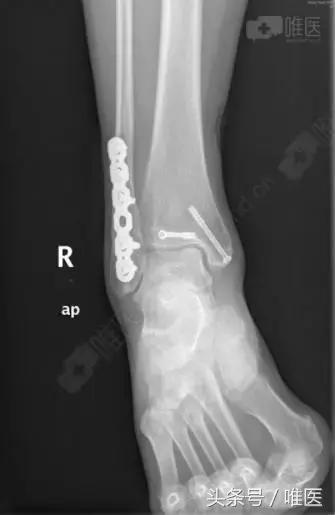

手术名称:右踝关节骨折切开复位内固定术。

右踝关节骨折切开复位内固定术

全身麻醉成功后,取左侧卧位,右下肢常规消毒铺巾,右外踝后外侧切口长约8cm切开皮肤、深筋膜,自拇长屈肌及腓骨长短肌间隙进入,暴露外踝及后踝骨折块,复位后踝骨折块后予克氏针临时固定,纠正腓骨远端骨折外移及短缩畸形,克氏针临时固定,透视外踝及后踝骨折复位良好,取合适长度的后侧解剖锁定钢板螺钉牢固固定外踝,空心螺钉固定后踝,再次透视骨折复位及内固定位置良好,冲洗缝合外侧伤口,取仰卧位,右内踝弧形切口切开暴露内踝骨折块及内侧间隙,术中见内踝骨折移位,内侧间隙内碎骨块游离,清理内侧间隙,复位内踝骨折后予导针固定,透视骨折复位及导针位置良好,取34mm长度的4.0 空心螺钉牢固固定,透视骨折复位及内固定位置良好,冲洗伤口,缝合,术中出血约100ml,未予输血。术中伤口予罗哌卡因+得宝松局部镇痛治疗。手术顺利,病人送PACU。

治疗后影像